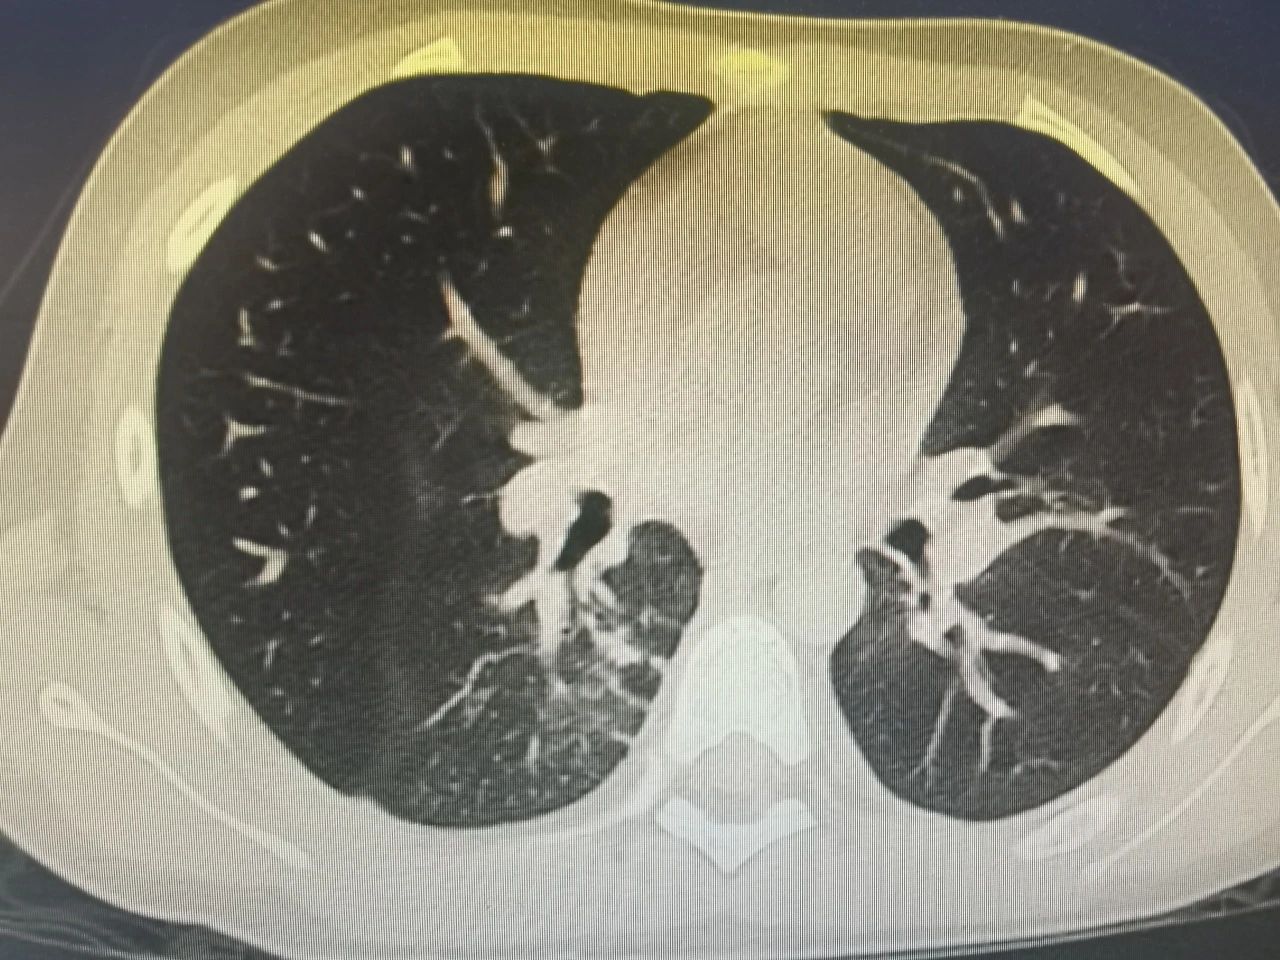

半个多月前,一名9岁的小男孩七七在父母的陪伴下,来到了锦州市妇婴医院(妇幼保健院)小儿呼吸科。因为反复高热、咳嗽10天,辗转于外院治疗6天,病情却逐渐加重,反复39-40度不退,复查的肺CT提示重症肺炎。

接诊后,当班的齐思梦医生敏锐地捕捉到重要信息:每天有将近40度的高热,持续10天;经过正规抗炎治疗6天,完全无效;合并有胸腔积液。

种种迹象表明,这是一个重症,必须积极处理。于是,在入院后的第一时间内,齐医生立即完善相关检查,并积极抗感染、雾化、营养支持等治疗,但孩子的病情仍在进一步进展。夜间,这个小男孩出现了呼吸急促,经皮血氧饱和度下降,这时候,血化验结果陆续回报,炎症指标飙升,血凝指标近10倍增高……马上吸氧,抗凝等对症处置。与刘铁英主任和王晓巍副主任沟通会诊,科室迅速召开重症讨论,定下治疗方案。齐医生耐心详细地向家属交代患儿目前需行支气管镜介入治疗,得到家属的签字同意后,于入院第2天即完成了第一次支气管镜介入治疗, 30分钟后孩子就安全返回病房,术中吸出3个较大的“树枝样”塑型痰栓及数个小痰栓。术后当晚,孩子精神状态明显好转,食欲增加,家属高兴的对医生们说:“你们太厉害了,这一天就精神了”。

在医护人员精心的治疗和护理下,七七一天比一天见好,这期间七七又做了2次支气管镜进行“洗肺”,把积存于各个小气管、“小枝儿”里的痰栓彻底清理后,七七的体温逐步下降到正常,呼吸也逐渐平稳。从一开始的抗拒,到后来做完支气管镜能和齐医生们说谢谢,小七七也表现出了惊人的勇敢和坚强、懂事。

节假日期间,七七出现了间歇性胸痛,疼出了眼泪,又出现了一次低热,家属的心再一次提到了嗓子眼儿。刘铁英主任连忙赶到医院看望他,担心重症肺炎可能出现恢复期的肺栓塞,又紧急联系放射线,放射线曹主任马上安排会诊给他急查了肺增强CT。结果出来后没有发生栓塞,医护人员和家属都松了一口气,考虑跟胸水吸收后引起的胸膜牵扯痛有关系,对症处置后2-3天胸痛消失,发热也很快消失。